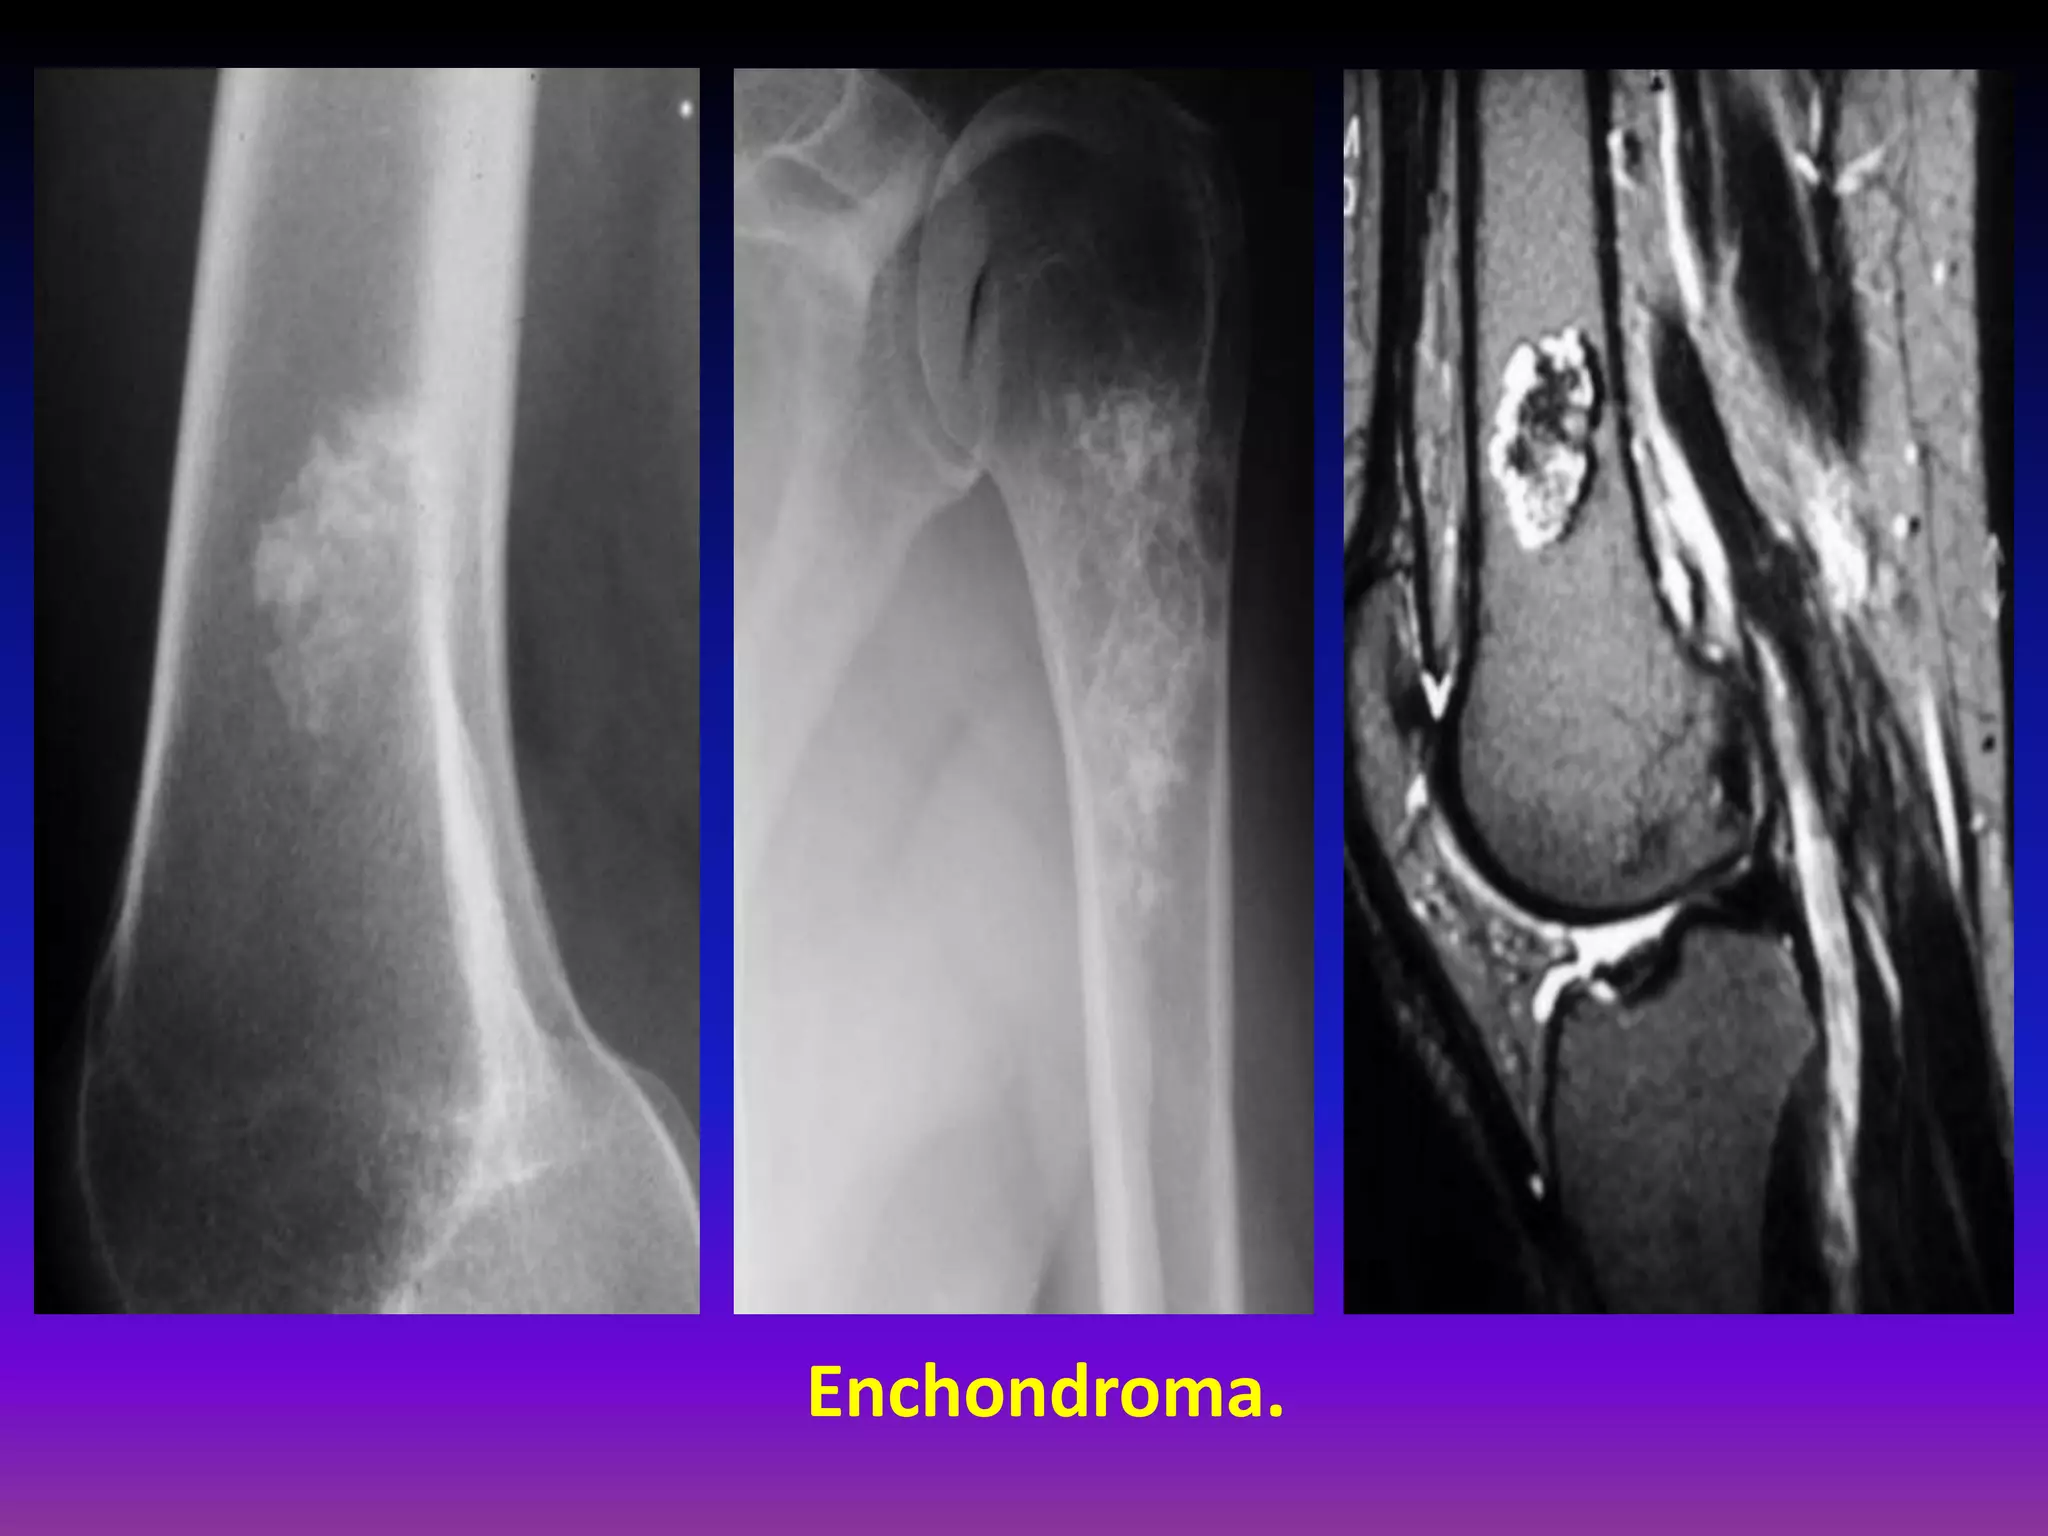

Enchondroma.

Solitary, benign,

intramedullary cartilage

forming tumor

Peak incidence in 3 3rd rd

decade

Male : female = 1 : 1

Common in short tubular

bones of hands and feet

Most common primary

tumor in the hand,

usually in the diaphysis.

Clinical Presentation.

Hand > Foot lesions more commonly active.

Cortical bone erosion resulting in pain, bony mass,

or pathologic fracture.

Expansile lesions may cause palpable bony mass

Found incidentally in long bone .

< 1% risk of malignant transformation< transformation.

Radiographic Appearance.

Long bones.

Metadiaphysis.

Most common in femur and humerus.

Tubular bone Diaphysis Matrix – “popcorn ”

“comma shaped ”

“stippled” calcification.